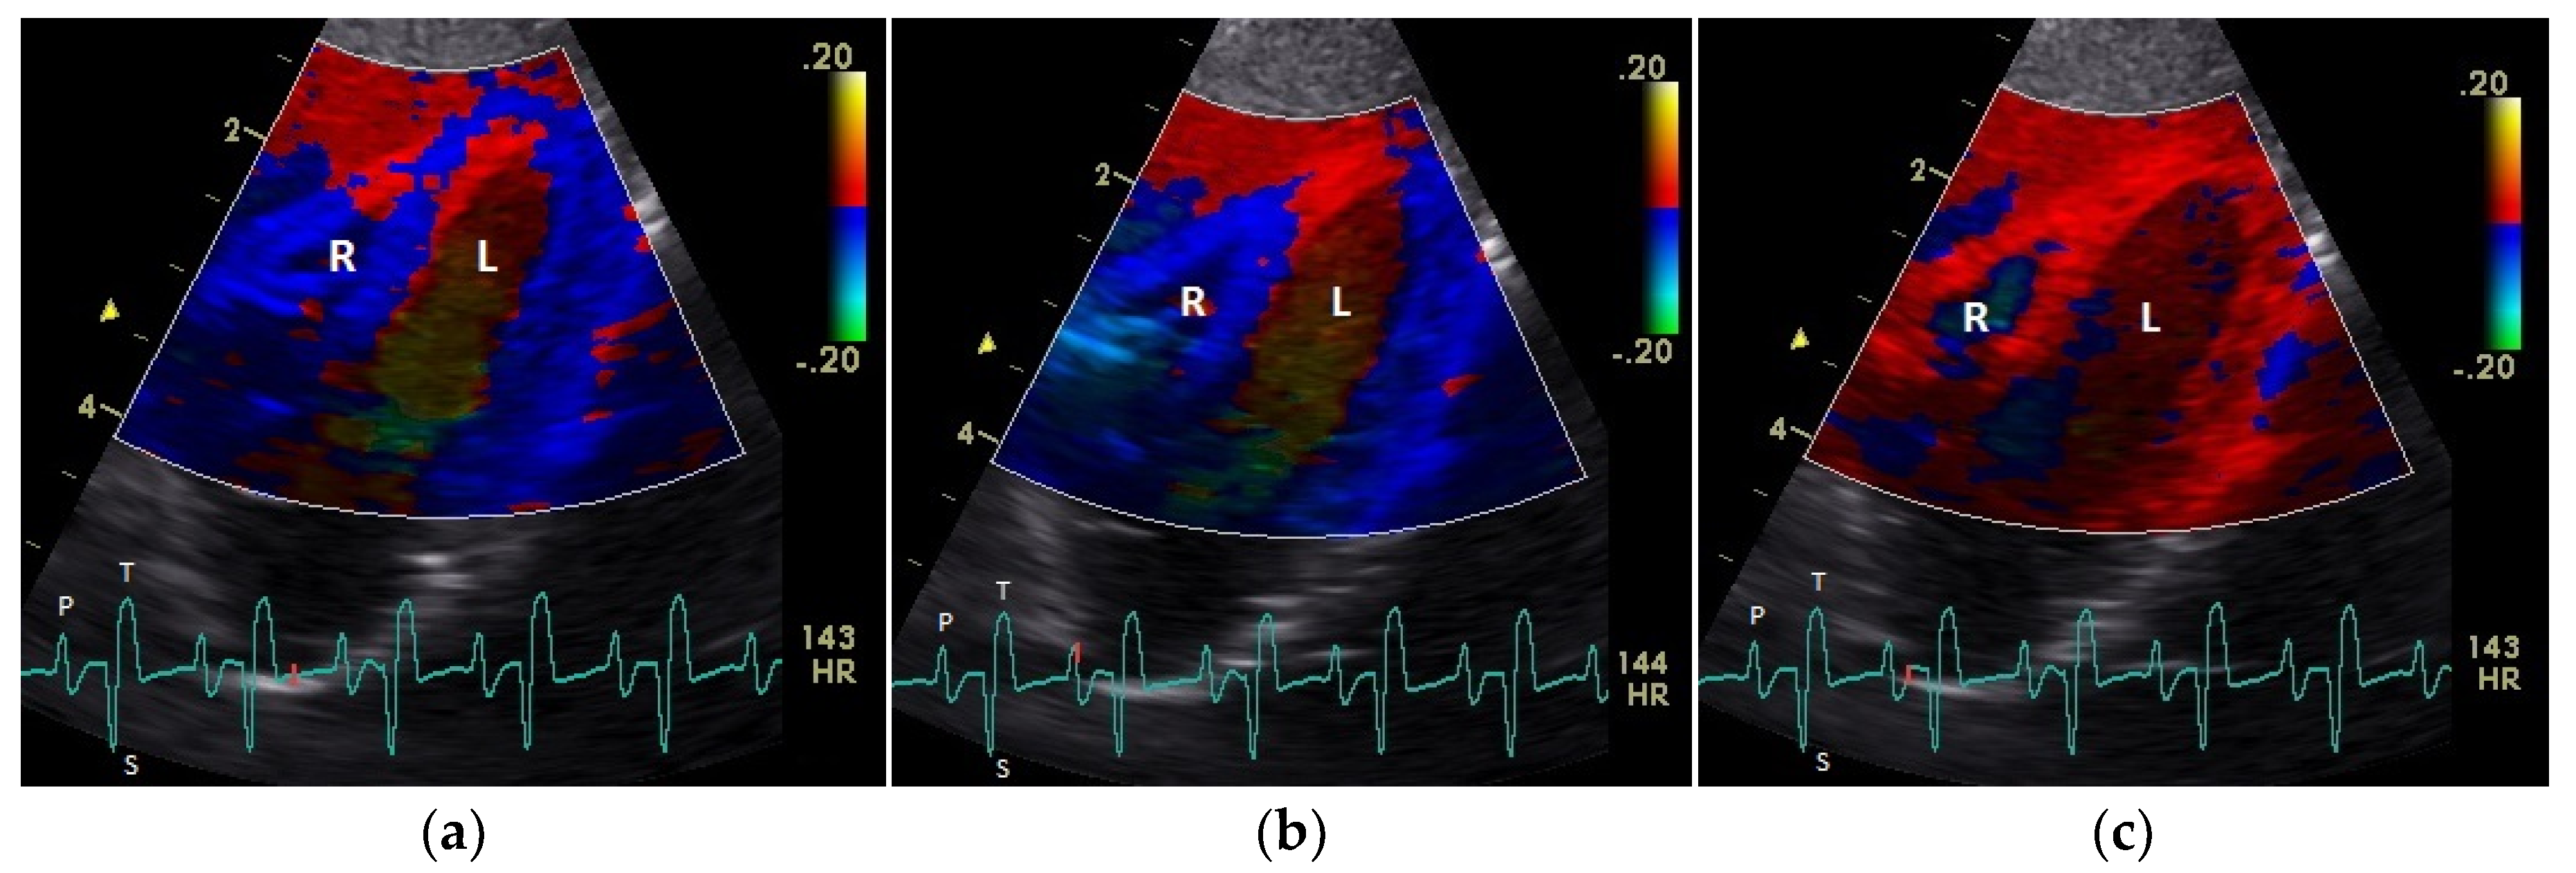

Figure 1.

Color coding of early (a) and active diastolic (b) tissue velocities and a part of the myocardial movement during the isovolumetric contraction (c) by tissue Doppler imaging in the four-chamber view: the movement of the myocardium toward (red color) and away from the heart apex (blue color) is visible. R: right; L: left ventricle; HR: heart rate. Electrocardiogram: P: P wave; S: S wave; T: T wave. The color scale on the right of the image is calibrated in cm s−1.

The positive S’ wave of the TDI curve (Figure 3 and Figure 4; ascending part of the S wave to the descending part of the T wave of the ECG) describes the systolic movement of the heart base toward the heart apex and represents the expulsion phase of the heart. In the middle of the S’ wave of the TDI, there is little movement of the heart apex toward the heart base and the myocardial velocities are negative (Figure 2). This movement in the middle part of the systole led to an irregular shape of the S’ wave in the TDI curve (Figure 3). The negative E’ wave (Figure 3 and Figure 4; after the T wave of the ECG) in the TDI curve describes the movement of the myocardium during the passive ventricular filling and the second negative A’ wave of the TDI curve (Figure 3 and Figure 4; P wave of the ECG) describes the movement of the myocardium in the active filling phases of the heart during the diastole away from the heart apex. Before and after the S’ wave, the TDI curve showed undirected deflections as a sign of isovolumetric contraction (IVC) and relaxation (IVR; Figure 3 and Figure 4). However, the transition between the A’ and S’ waves (IVC) and the S’ and E’ waves (IVR) could be flowing and sometimes difficult to see.